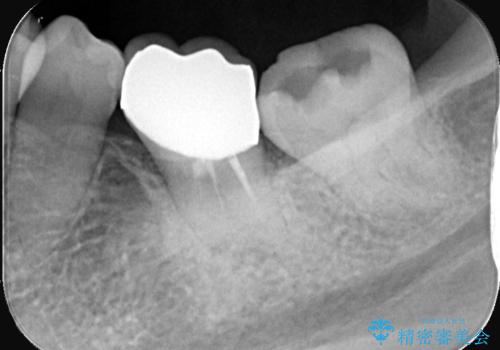

- 銀歯が取れたとのことで来院されました。中で虫歯が広がっている状態でした。材料の特徴を説明し、セラミックインレーでの修復となりました。

接着時にはラバーダム防湿を行いました。